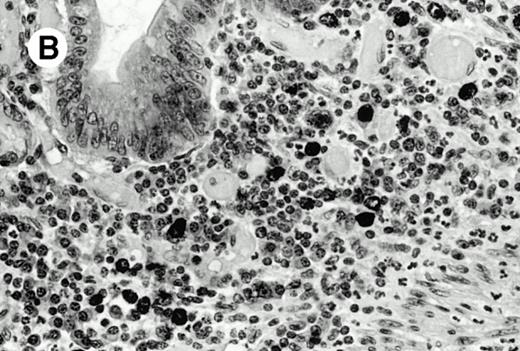

Three cases (cases no. 1 to 3) were located in the nasal cavity. The neoplastic infiltrate consisted of medium and/or large pleomorphic lymphoid cells (Fig 1)intermingled with variable numbers of small lymphoid cells, plasma cells, eosinophils, and histiocytes. Features of angiocentrism and angioinvasion, epitheliotropism, and areas of necrosis were observed in all three cases. Patient no. 4 presented with disease restricted to the lung and an open-lung biopsy was available. The neoplastic infiltrate was composed of large atypical lymphoid cells and was predominantly interstitial without extensive destruction of the normal architecture. Features of angiocentrism, angioinvasion, and epitheliotropism were present (Fig 2A and B). Case no. 5 involved the larynx, extending to the piriform sinus, the ventricle, and the arytenoid. One month later, the lymphoma disseminated to the subcutaneous tissue in the spinal region and biopsy specimens from both sites were available. The neoplastic cells were medium and large, with abundant clear cytoplasm and slightly irregular nuclei with dense chromatin. Epitheliotropism was present in the larynx mucosa. Small foci of necrosis and angiocentrism were seen without angioinvasion. Three patients presented with cutaneous disease. Cases no. 6 and 7 were comparable, as both histories started with necrotic subcutaneous nodules of the thigh, which on histologic analysis were characteristic of cytophagic histiocytic panniculitis without evidence of lymphoma (Fig 3A). Second excisional biopsies of cutaneous nodules obtained 7 and 5 months later, respectively, showed characteristic features of lymphoma in both cases (Fig 3B). However, in case no. 6, skin biopsy specimens showed an epidermotropic PML lymphoma extending to the dermis and the subcutaneous tissue, whereas in case no. 7, the neoplastic infiltrate consisted of a PSC confined to the subcutaneous tissue, admixed with benign histiocytes that showed phagocytosis. Patient no. 8 presented with recurrent skin lesions with spontaneous remission over a period of 10 years. The initial skin biopsies demonstrated an intense epidermotropic neoplastic infiltrate that extended to the superficial and deep dermis composed of atypical PML cells. All cutaneous cases displayed features of angiocentrism, but angioinvasion was observed only in case no. 6 and foci of necrosis in cases no. 6 and 8.

Subcutaneous γδ T-cell lymphoma (case no. 6). (A) Initial biopsy sample shows characteristic features of cytophagic histiocytic panniculitis without evidence of lymphoma cells; (B) second biopsy performed 7 months later demonstrates involvement of the subcutaneous tissue by a pleomorphic γδ T-cell lymphoma (hematoxylin-eosin stain).

Subcutaneous γδ T-cell lymphoma (case no. 6). (A) Initial biopsy sample shows characteristic features of cytophagic histiocytic panniculitis without evidence of lymphoma cells; (B) second biopsy performed 7 months later demonstrates involvement of the subcutaneous tissue by a pleomorphic γδ T-cell lymphoma (hematoxylin-eosin stain).